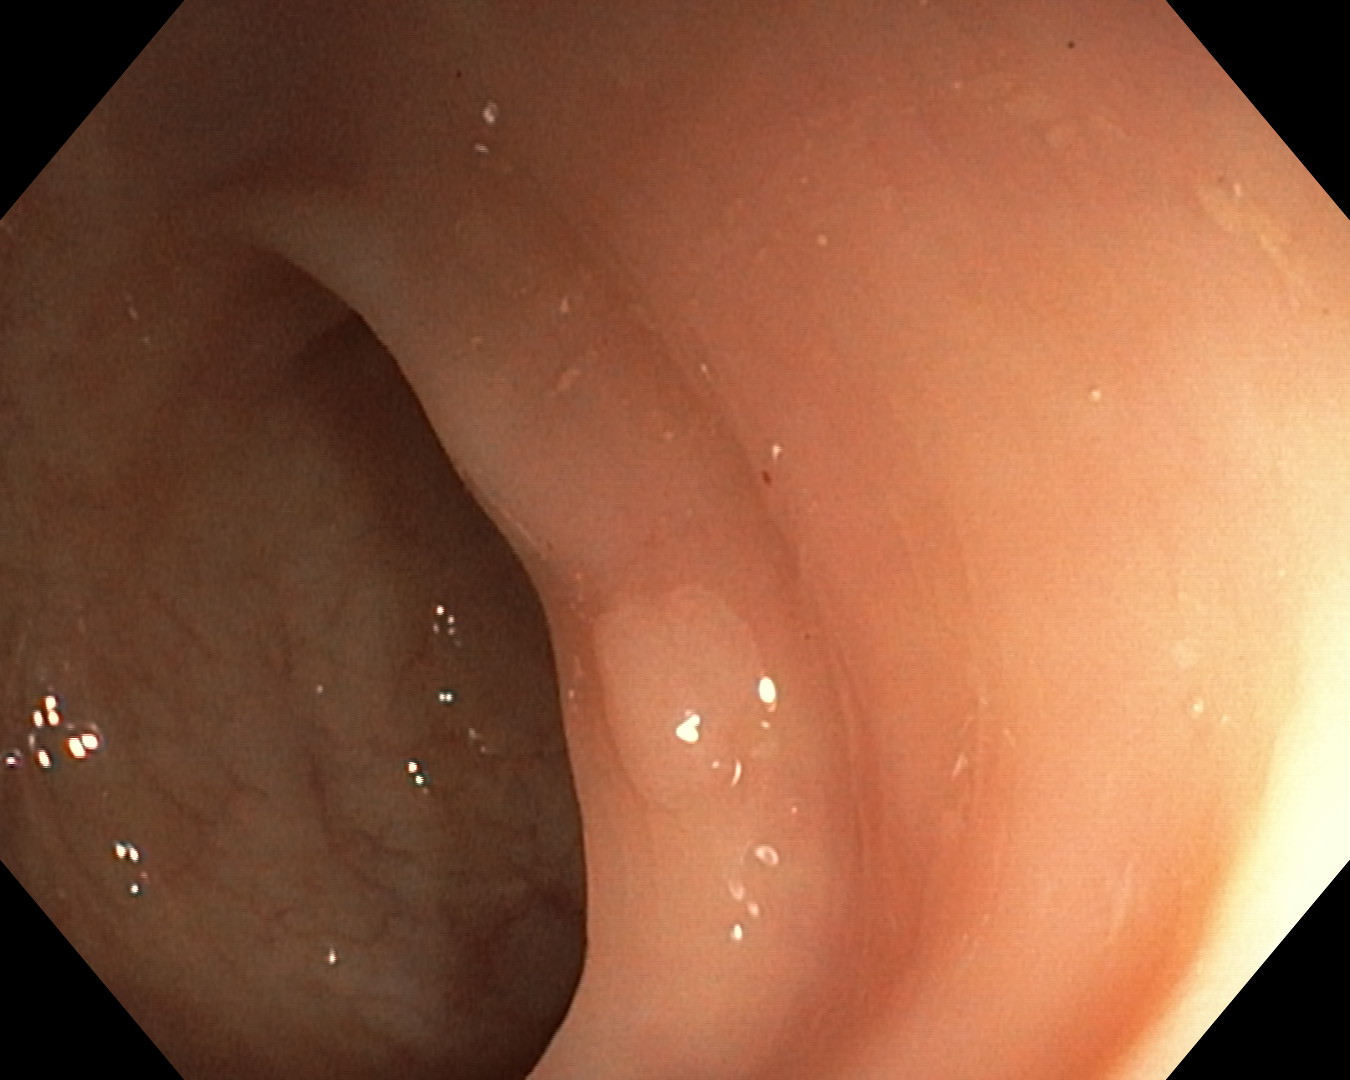

As part of the EndoCV2021 challenge (https://endocv2021.grand-challenge.org/), we were tasked with creating machine learning models that automatically segment polyps [11, 12, 13] in video frames collected from real-world endoscopies. This is a complex task as polyps come in various shapes and sizes, where some (e.g., flat lesions) are barely detectable by even the most experienced endoscopists. Figure 1 shows some of the more difficult examples taken from EndoCV’s development dataset [10] provided by the challenge organizers. The challenge presented two separate tasks, the detection generalization challenge and the segmentation generalization challenge. We participated in the segmentation generalization challenge, where we achieved the best results among 13 other competitors in both rounds. The code for the experiments presented in this paper is available on GitHub111https://github.com/vlbthambawita/divergent-nets.

Figure 4 shows some example masks predicted by our best performing model (DivergentNets) together with masks produced by the intermediate models. We see that each intermediate model learns slightly different features, making an overall more precise segmentation mask when combined. For example, the first row of Figure 4 shows the predicted masks and ground truth of a large polyp. We see that each model predicts slightly different masks for the same input and that TriUNet over-estimates the size of the polyp. After averaging the predicted masks for DivergentNets’ final output, this area is smoothed out by the predictions from the other intermediate models.

Even though DivergentNets primarily produces more accurate masks than any single model, there are cases where masks from the intermediate model better match the ground truth. We see this in row three, where DeepLabv3+ produces a more precise mask than all other intermediate models, making the averaged output less accurate.